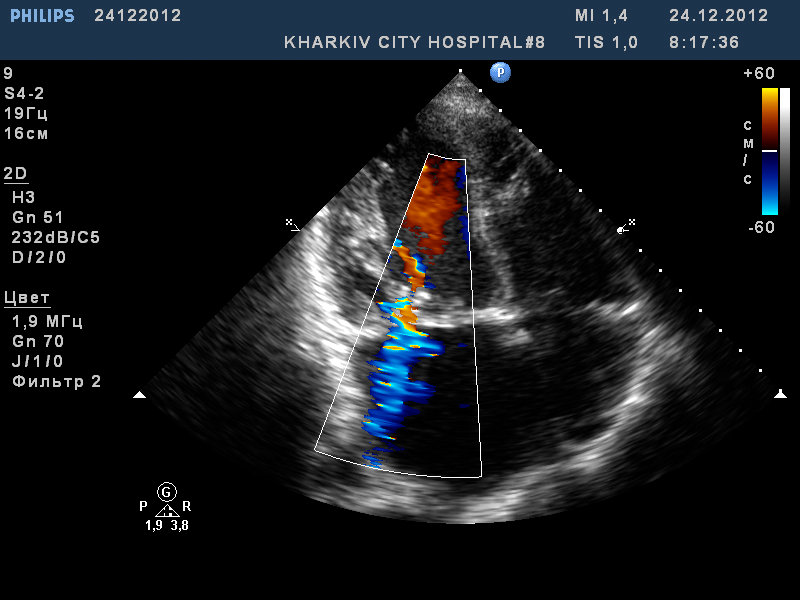

Пациент 52 лет. Поступил с нарушение ритма.

Заключение узи : склеротические изменения аорты, фиброзные изменения створок аортального клапана, незначительная недостаточность аортального клапана, частичный отрыв хорд передней створки митрального клапана, значительный митральный стеноз, умеренная МН, дилатация левого предсердия (6,0см), гипертрофия левого желудочка.